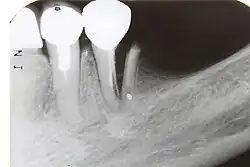

| A broken upper front tooth. The layers of tissue that make up the tooth are clearly visible, with the pink pulp standing out against the paler dentine and tooth enamel. | |